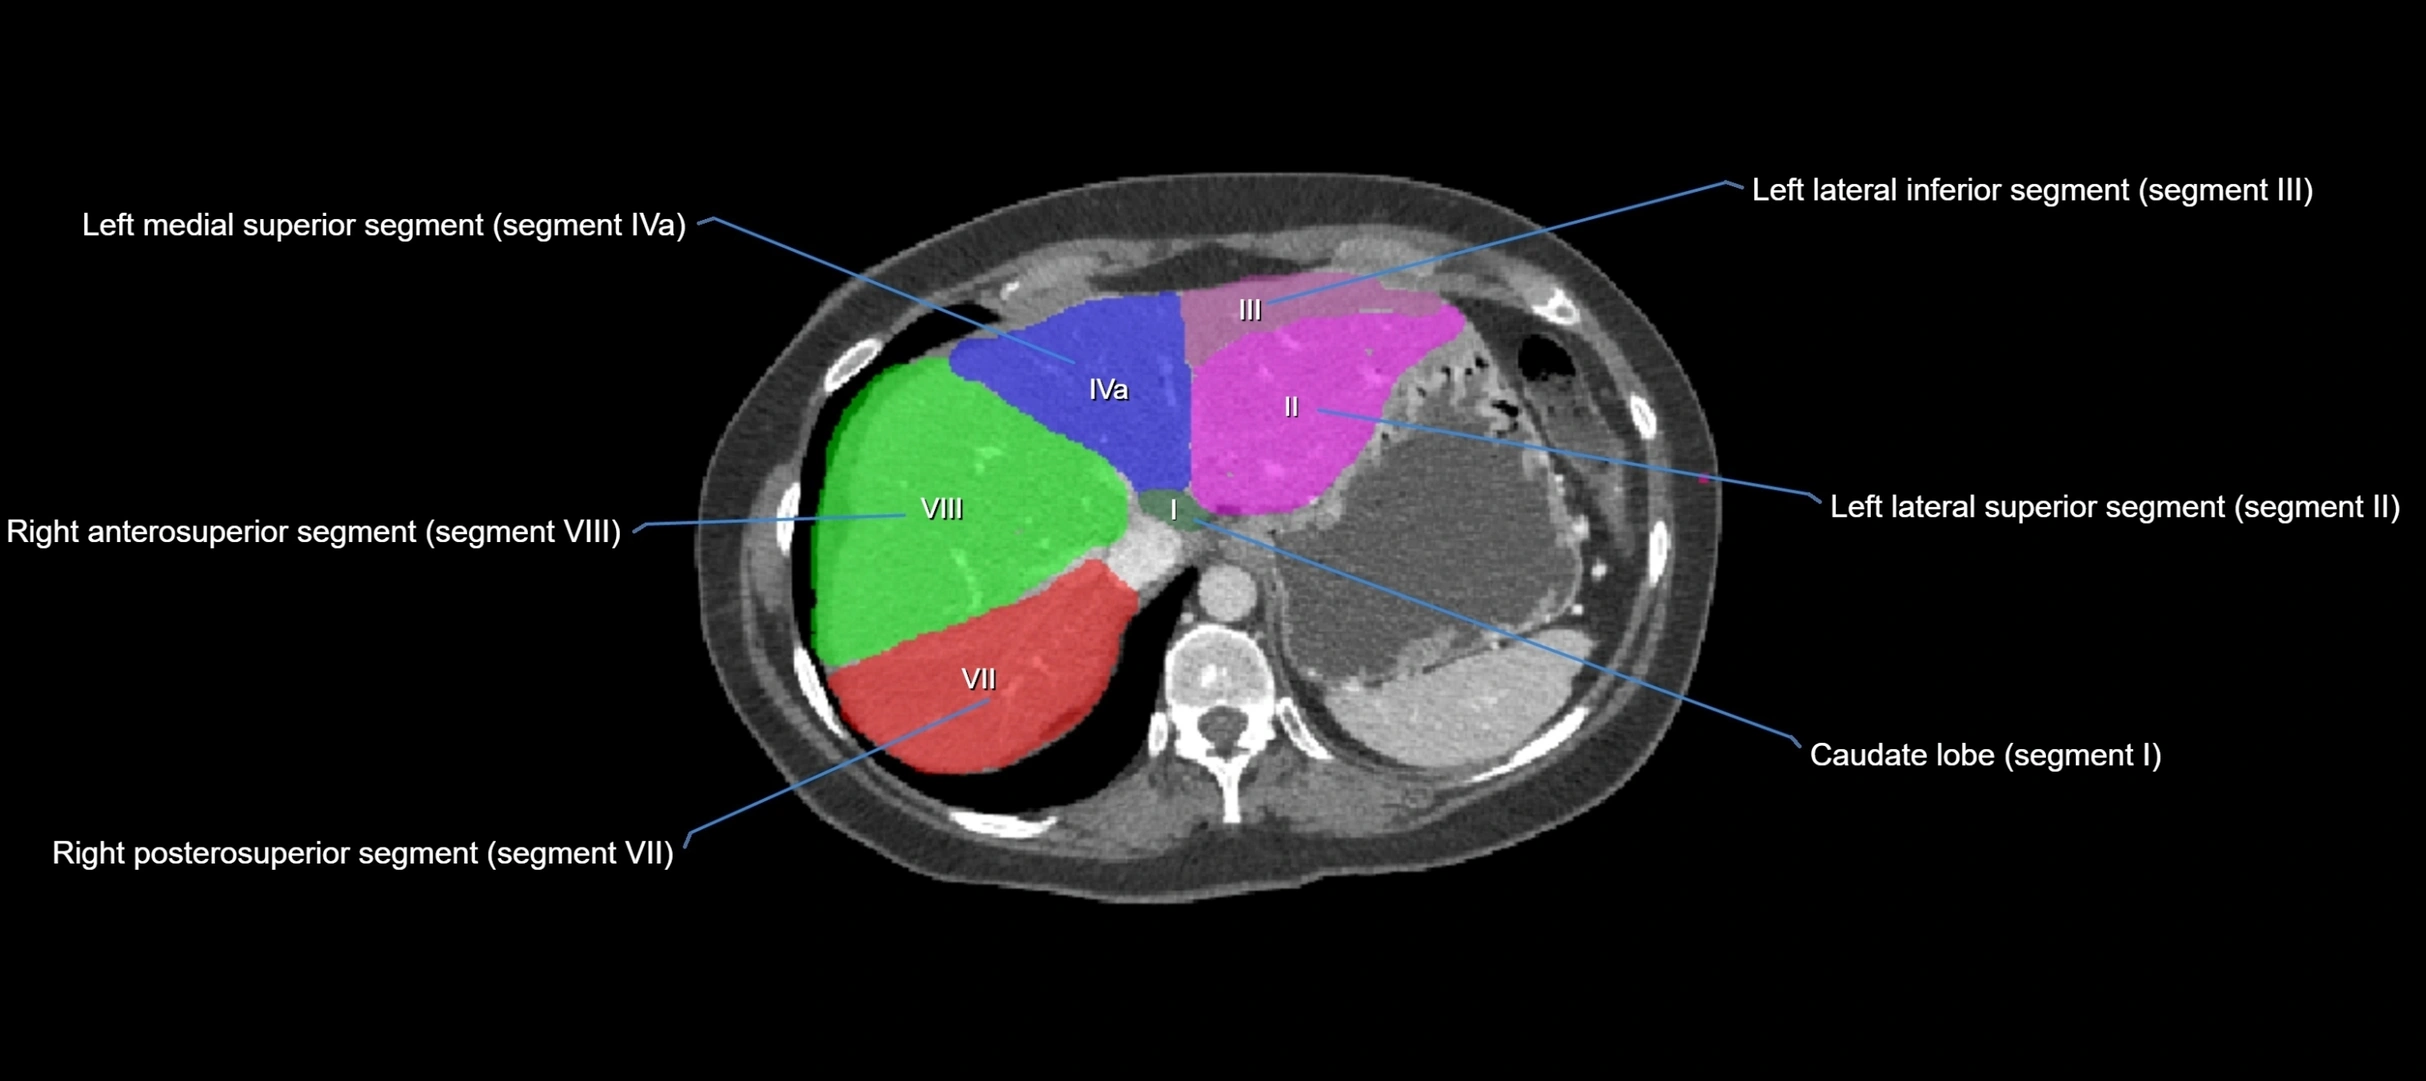

The caudate lobe of the liver is a distinct anatomical subdivision of the liver, designated as segment I in Couinaud’s classification. It lies on the posterior surface of the liver, between the fissure for the ligamentum venosum (left boundary) and the groove for the inferior vena cava (IVC) (right boundary). Superiorly, it is related to the posterior liver surface, and inferiorly it is separated from the left lobe by the porta hepatis.

The caudate lobe is unique because it receives dual portal venous and arterial inflow from both the right and left portal veins and hepatic arteries. It also has independent venous drainage directly into the IVC via multiple small hepatic veins, unlike other lobes that drain through the three main hepatic veins.

CT Image

image